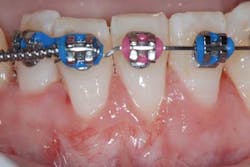

Preop: Alloderm (acellular dermal matrix), Emdogain, Coronally Advanced Flap (Tunneling Procedure)